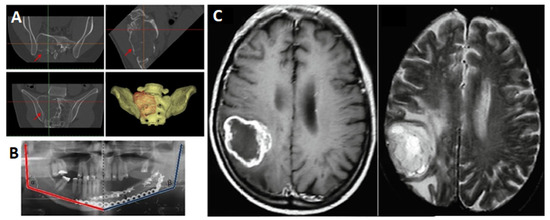

The acquired medical images saved in the internationally known format DICOM will allow opening the files basically all over the world, using all software (open source and commercial alike) dedicated to work with medical imaging. One of the important features of medical imaging, influencing the correct segmentation and design of the model, is slice thickness and slice spacing [24]. Currently, devices such as magnetic resonance imaging (MRI) or computed tomography (CT) allow for obtaining high image resolutions. Thanks to this, even during a routine scanning protocol, values for layer thicknesses from 0.6 mm to 2 mm and voxel sizes from 0.2 mm to 0.6 mm are obtained [24]. Layer thicknesses below 1 mm and voxel isotropy allow minimising the probability of the partial volume effect in the further design stages [25]. Obtaining the lowest possible layer thickness values during imaging gives great opportunities for reliable imitation of the 3D reconstructed organ, while maintaining high dimensional and shape accuracy. However, it should be considered that in the case of computed tomography, the thinner the layer, the higher the level of radiation delivered to the patient’s body. Therefore, when imaging structures with larger and less complex shapes, such as long bones or the pelvis, 2 mm thick layers are sufficient to obtain accurate models. However, in the case of more complex structures, such as a craniofacial surgery’s case, thinner layers, from 0.5 mm to 1mm, are recommended [26]. The selection of imaging is primarily determined by the physician, but magnetic resonance imaging better presents soft tissues, such as blood vessels or the brain, and this translates into better results during segmentation. In the case of bone tissue, computed tomography imaging works better, providing a clear separation of grey tones between calcium-based tissues, such as teeth and bones, and other types of tissues [27]. Examples of the use of medical images in design procedures are shown in Figure 4.

Figure 4. Examples of different use of medical imaging: (A) CT images of the pelvis and the generated 3D model [28], (B) measurements taken on X-ray medical imaging after mandibular reconstruction surgery [29], (C) MRI of the brain [30].